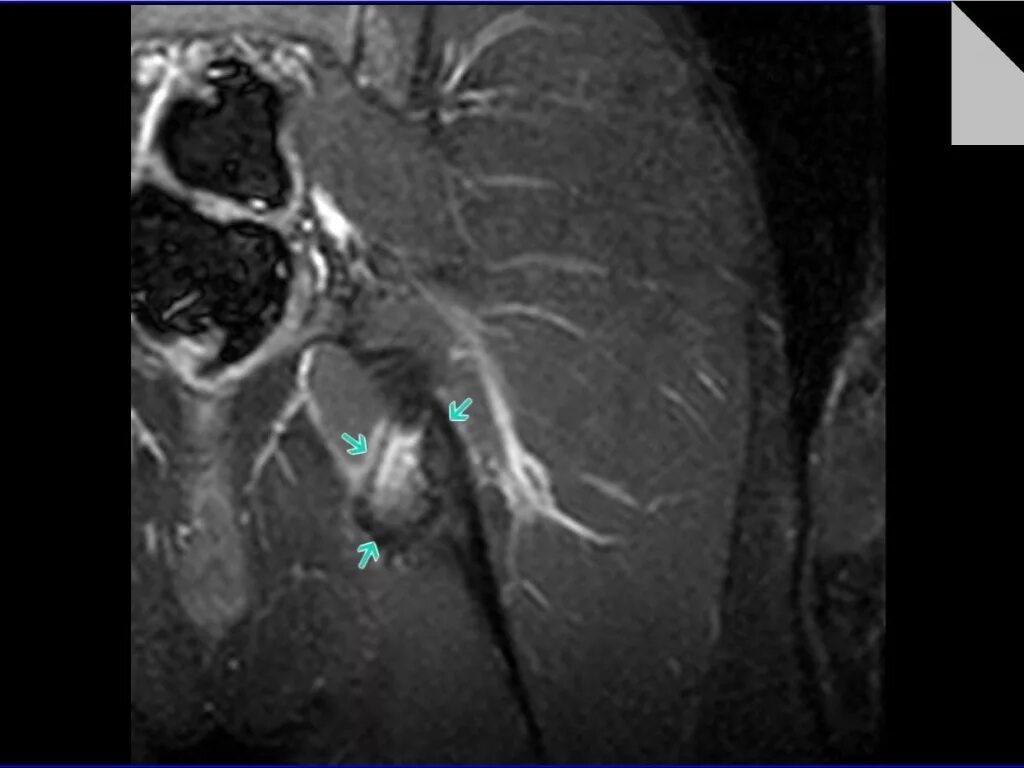

Хамстринг синдром тазобедренного сустава